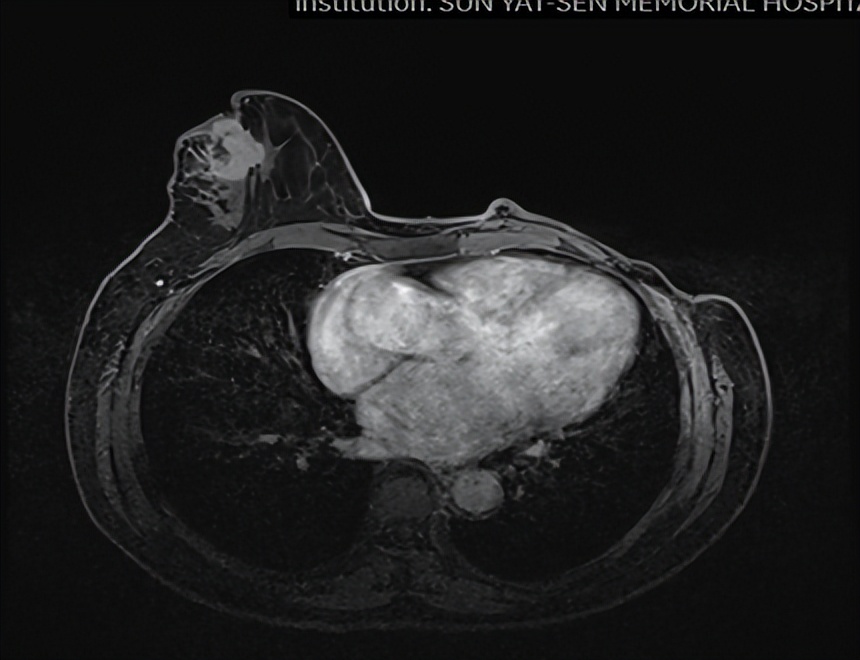

乳腺MR

右侧乳头后侧中部多个异常信号结节(较大者23*15mm),符合乳腺癌,BIRADS:5类。右侧腋下肿大淋巴结,考虑转移。

心脏彩超

房颤所致心脏改变:二尖瓣瓣环扩张并重度反流:三尖瓣瓣环扩张并中度反流:中度肺动脉高压;主动脉瓣、肺动脉瓣轻度反流;左室收缩功能偏低(LVEF50%);右室收缩功能正常。